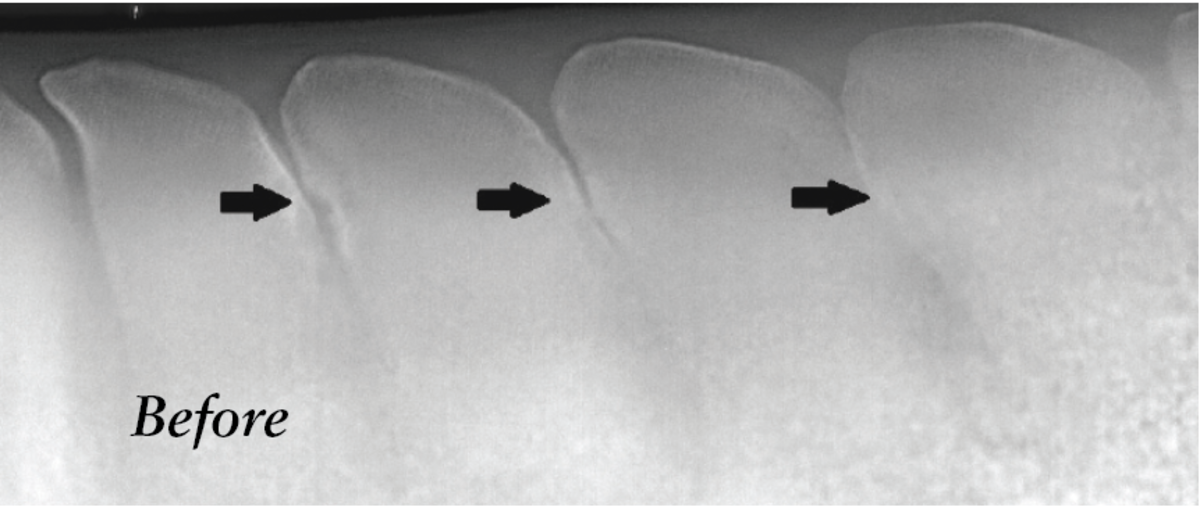

Osteoplasty. During this surgery, the vet reshapes the spinous processes, essentially shaving off some of the bone. “If the horse has bone-on-bone or overlapping bone, we can take out a small segment of the bone to widen the space,” explains Dr. Davis. Simultaneously, the vet will also perform the ISLD procedure, he notes. This is a more invasive surgery with a longer recovery period.

Ostectomy. “This is basically an osteoplasty on steroids,” says Dr. Davis, explaining that this surgery removes more bone. “Instead of just widening the space, we take a bone saw and take out a significant portion of [the spinous process] or remove it almost in its entirety,” he says.

In some cases, the vet may actually perform more than one of these procedures during a single surgery. For instance, says Dr. Davis, “If the horse has four spots involved, I may widen one spot with osteoplasty and do an ostectomy to fix the next two at the same time. It depends on how severely impinging or misshapen or unhealthy the bone looks.”

Courtesy, Dr. Weston Davis